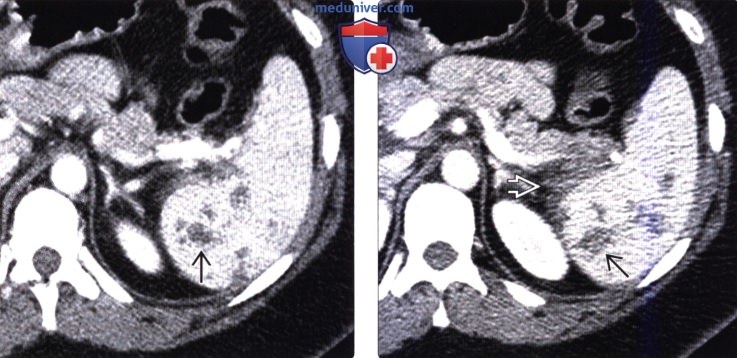

Селезеночный индекс на кт 104 фотографий